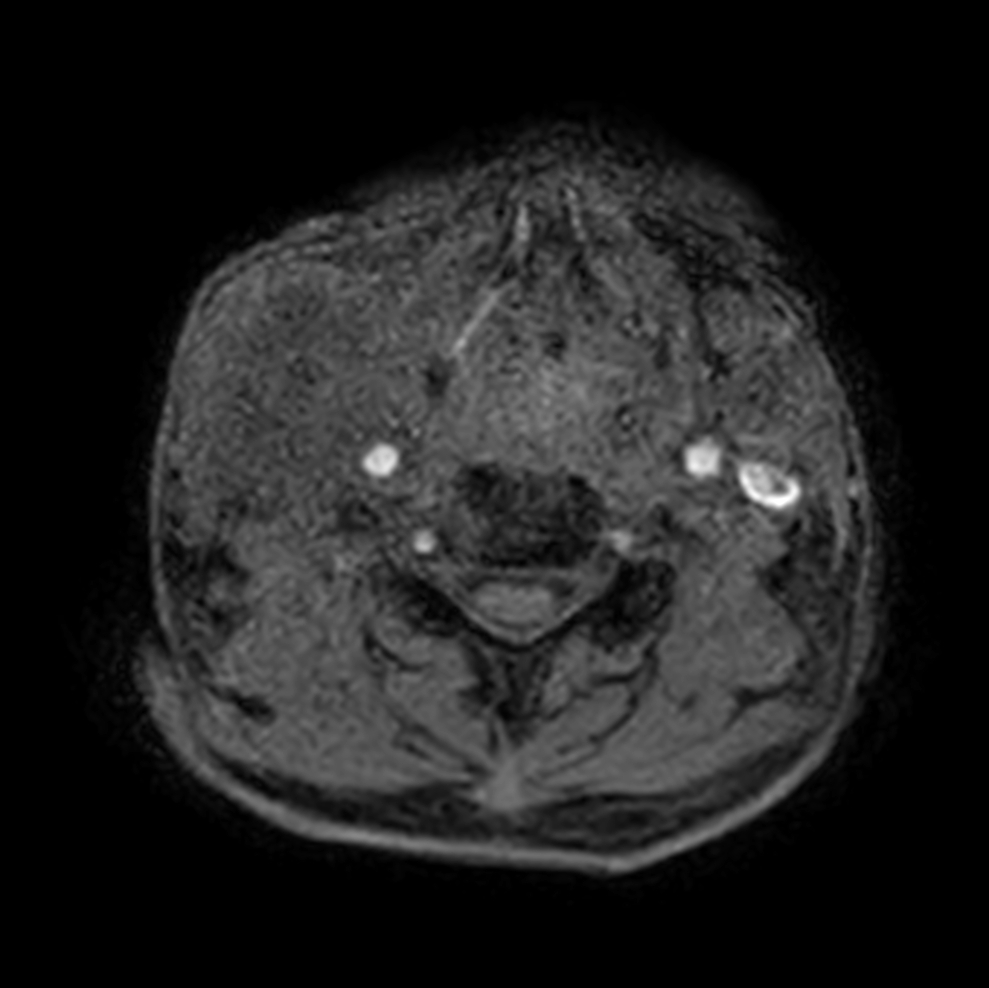

Axial DWIBS (b700)